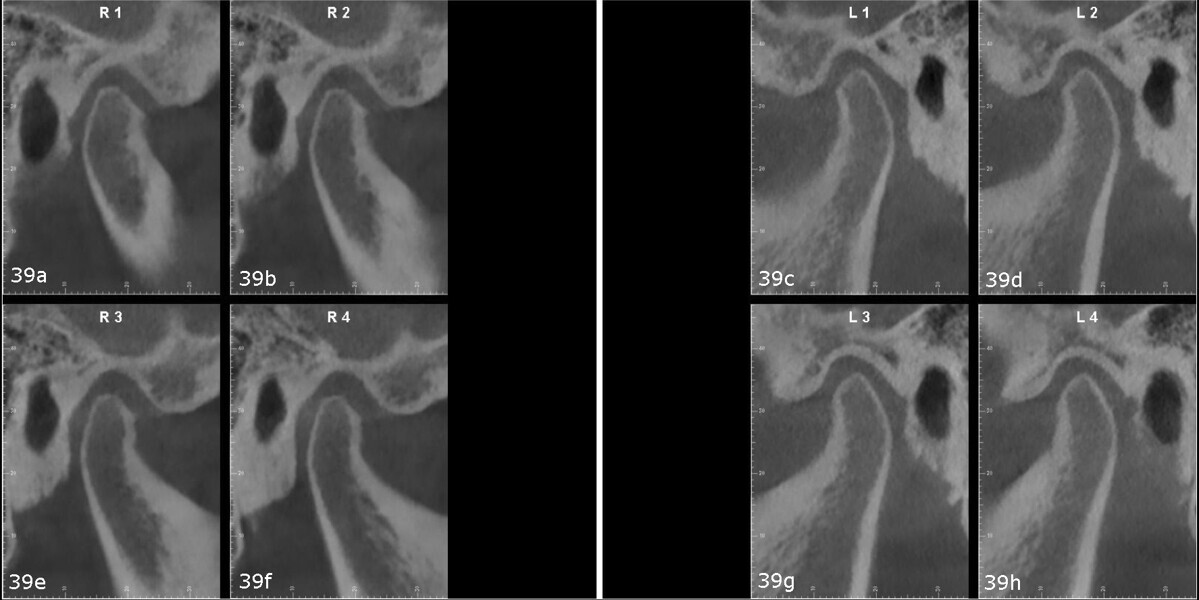

TMJ analysis

The patient reported joint and orofacial muscle pain, headaches, neck pain and nocturnal bruxism. CBCT imaging showed small condyles with flattened articular surfaces. The right condyle was slightly posteriorly positioned within the mandibular fossa (Fig. 39). Additionally, a virtual articulator mounting using the MODJAW system revealed that there was a significant discrepancy between maximum intercuspation and centric occlusion and that the first occlusal contact was at tooth #27 (Fig. 40).